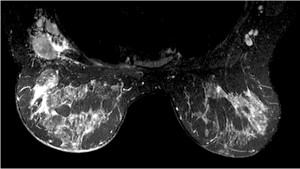

Con nuestra Nueva RM Digital podemos obtener resultados increíbles incluso en pacientes inquietos, presencia de artefactos de movimiento y Contraste de agua, grasa, en fase y fuera de fase en una sola adquisición para obtener imágenes libres de grasa.

Con adquisición de imágenes en T1W como VIBRANT/VIBRANT Flex, enhanced DWI, espectroscopia con BREASE MR, bobinas dedicadas de 16 canales de recepción y herramientas avanzadas de post-procesado para recabar toda la información que necesita para diagnosticar con total seguridad y lograr resultados positivos para sus pacientes.

Con la nueva RM digital podemos obtener imágenes de cada mama con saturación de grasa y además adquirir imágenes bilaterales en plano axial o sagital, lo que nos ha permitido mejorar de forma notable nuestro programa de diagnóstico por imagen del cáncer de mama.”